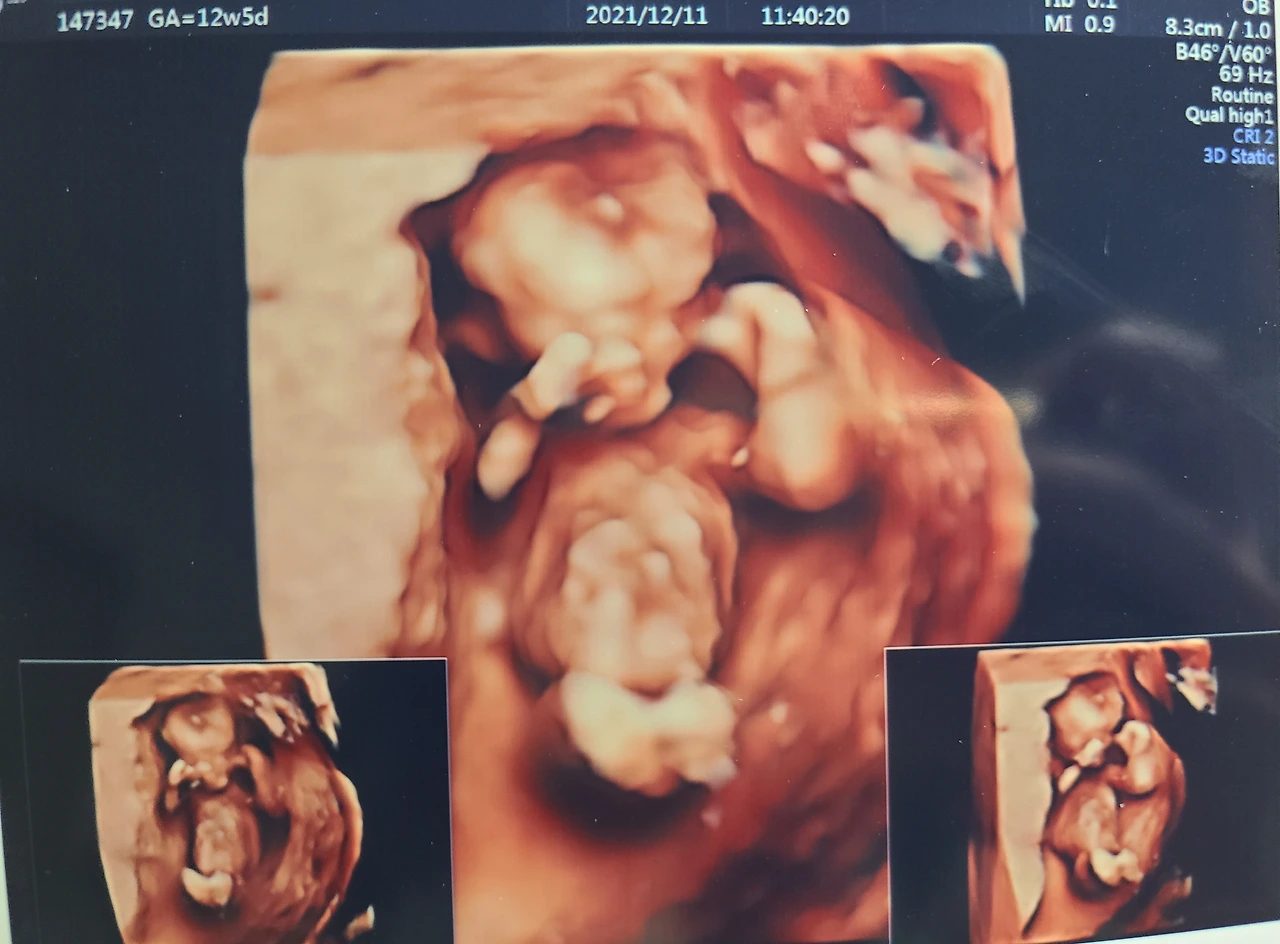

임신 12주에서 27주 사이는 임신 10개월의 기간 중 가장 안정된 시기라고 해서 임신 황금기라고도 불리는 기간이야. 엄마는 11주 차에 난임병원을 졸업하고 황금기가 시작되는 12주 차에 일반 분만병원으로 옮겨 첫 진료를 보았어. 정밀 초음파로 만난 너는 두 손으로 얼굴을 모두 가리고 있었지만 그 귀여움은 전혀 가려지지 않고 드러났어.

정밀 초음파로 확인한 목투명대에도 이상이 없고 모두 너무 좋다는 의사선생님의 활기찬 목소리가 아직도 기억나. 그렇게 너와 나는 평범한 태아와 산모로 임신 정규 트랙에 멋지게 함께 오른 거야. 우리가 남은 기간도 아름다운 팀플레이를 보여줄 수 있겠지?